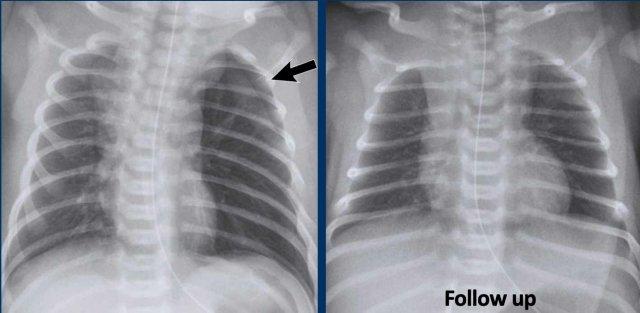

Trẻ sơ sinh, tuổi thai 27 tuần, được điều trị vì hội chứng suy hô hấp (RDS).

Lúc 2 ngày tuổi đột ngột có diễn biến xấu đi.

Hình 1

Các đám mờ dạng lưới nốt hai bên phù hợp với hội chứng suy hô hấp cấp ở trẻ sơ sinh (IRDS), được điều trị bằng thở áp lực dương liên tục (CPAP).

Hình 2

Ở ngày tuổi thứ 2, phim X-quang cho thấy các vùng thấu quang tỏa ra ở phổi trái do khí thũng mô kẽ phổi (PIE).

Những hình ảnh này là của một trẻ sơ sinh tuổi thai 32 tuần, được điều trị vì Hội chứng suy hô hấp (RDS).

Một số biến chứng đã phát triển, bao gồm tràn khí màng phổi bên trái, đã được dẫn lưu.

Sau

khi dẫn lưu, tình trạng bệnh nhân xấu đi.

Phim X-quang cho thấy hình ảnh thấu quang dạng bong bóng tỏa ra hai bên do khí thũng mô kẽ phổi (PIE) hai bên.

Biểu hiện này rõ hơn ở bên trái.

Trong quá trình theo dõi, trẻ cũng phát triển tràn khí màng phổi bên phải.